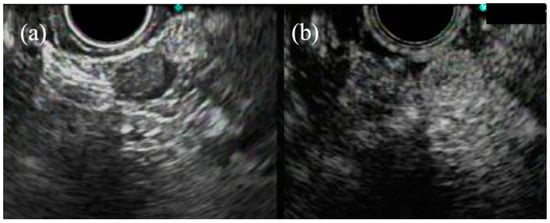

- Kanamori, A.; Hirooka, Y.; Itoh, A.; Hashimoto, S.; Kawashima, H.; Hara, K.; Uchida, H.; Goto, J.; Ohmiya, N.; Niwa, Y.; et al. Usefulness of contrast-enhanced endoscopic ultrasonography in the differentiation between malignant and benign lymphadenopathy. Am. J. Gastroenterol. 2006, 101, 45–51. [Google Scholar] [CrossRef] [PubMed]